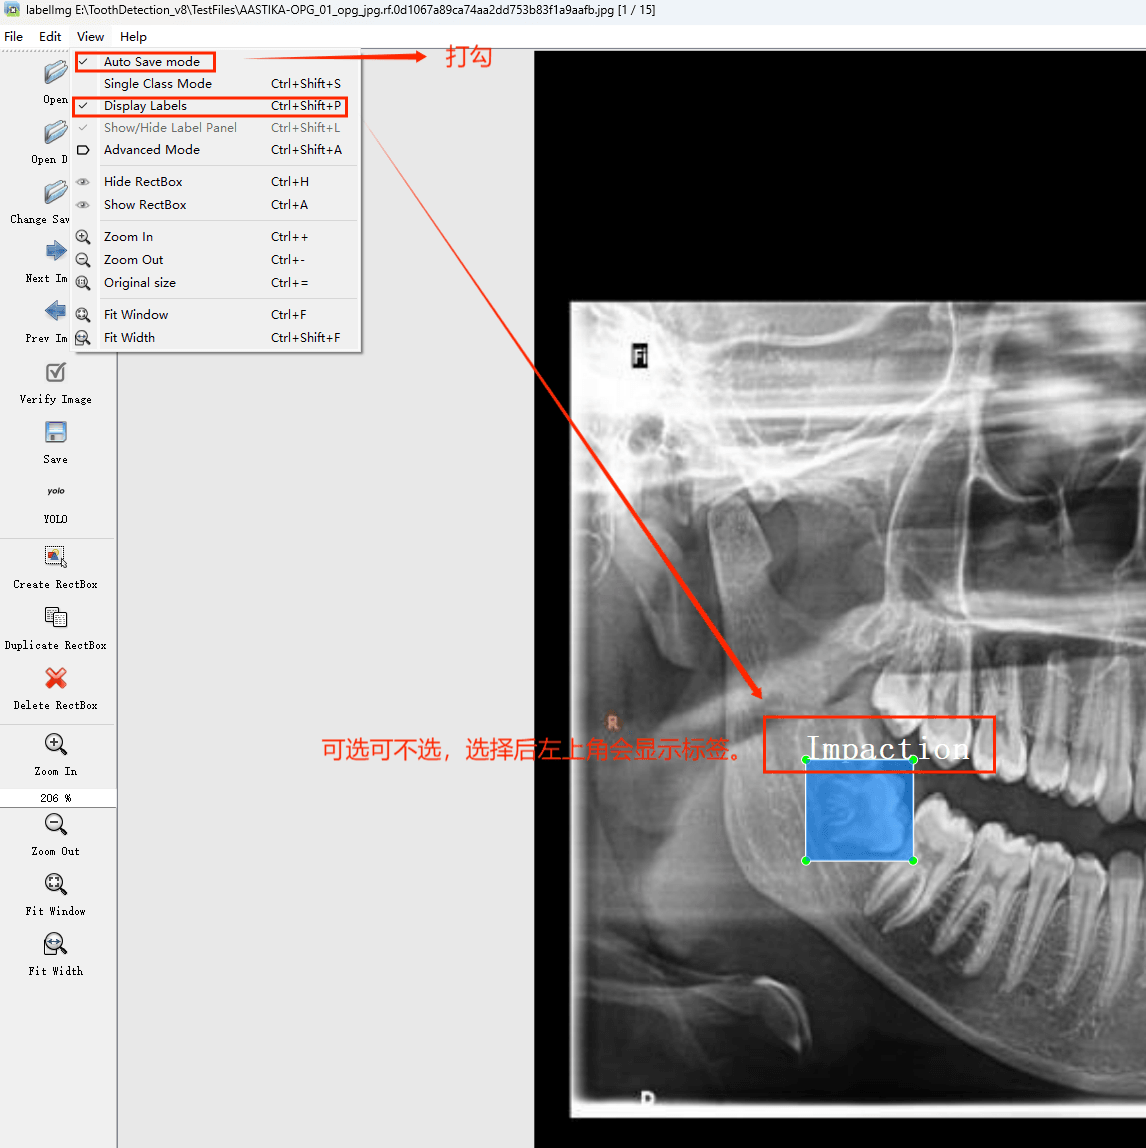

目标检测标注工具

(1)labelimg:开源的图像标注工具,标签可用于分类和目标检测,它是用python写的,并使用Qt作为其图形界面,简单好用(虽然是英文版的)。其注释以 PASCAL VOC格式保存为XML文件,这是ImageNet使用的格式。此外,它还支持 COCO数据集格式。

打开后,我们自己设置一下

在View中勾选Auto Save mode

接下来我们打开需要标注的图片文件夹

并设置标注文件保存的目录(上图中的Change Save Dir)

接下来就开始标注,画框,标记目标的label,然后d切换到下一张继续标注,不断重复重复。